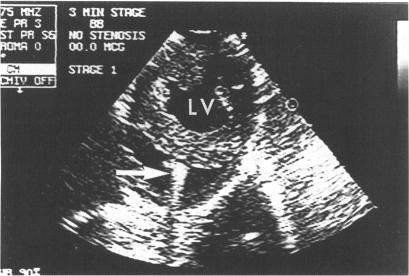

To evaluate the feasibility and ability of percutaneous transvenous intracardiac echocardiography (ICE) to image the left ventricle (LV) and monitor its function from the right ventricular (RV) cavity.

A 10 MHz catheter was advanced into the RV from the jugular vein and positioned along the septum at the LV papillary muscle level in five dogs. The catheter was manipulated until a stable catheter position along the septum, which provided on-axis images of LV, was obtained. Different states of LV size and systolic function (n = 80) were created with dobutamine or esmolol, both in the presence and absence of coronary stenoses. LV stroke area (cm2) obtained by ICE was measured at the mid-ventricular level and compared with stroke volume (cm3) obtained simultaneously with a transaortic flow probe. LV end diastolic, end systolic, and stroke areas obtained by ICE were also compared with those obtained by short-axis epicardial echocardiography.

In 96% of the stages, short axis images of the LV could be obtained and measured by ICE. LV end diastolic, end systolic, and stroke areas measured by ICE were not significantly different from epicardial echocardiographic values. Stroke area correlated with stroke volume in each dog (mean correlation coefficient 0.79 (SEE 0.19) cm2) (P < 0.001).

评估经皮经静脉心腔内超声心动图(ICE)从右心室(RV)腔对左心室(LV)成像并监测其功能的可行性和能力。

将一根10MHz的导管经颈静脉插入右心室,并在五只犬的左心室乳头肌水平沿室间隔定位。操作导管直至获得沿室间隔的稳定导管位置,该位置可提供左心室的轴位图像。在有和没有冠状动脉狭窄的情况下,使用多巴酚丁胺或艾司洛尔创建左心室大小和收缩功能的不同状态(n = 80)。通过ICE在心室中部水平测量左心室的每搏输出面积(cm²),并与经主动脉流量探头同时获得的每搏输出量(cm³)进行比较。通过ICE获得的左心室舒张末期、收缩末期和每搏输出面积也与短轴心外膜超声心动图获得的结果进行比较。

在96%的阶段中,ICE能够获得并测量左心室的短轴图像。ICE测量的左心室舒张末期、收缩末期和每搏输出面积与心外膜超声心动图的值无显著差异。每只犬的每搏输出面积与每搏输出量相关(平均相关系数0.79(标准误0.19)cm²)(P < 0.001)。